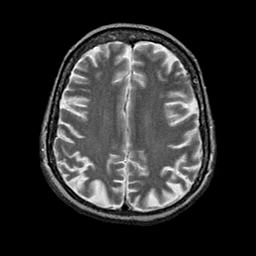

Alzheimer's disease: overlay -- Slice #17

[Home][Help][Clinical] Slice 17